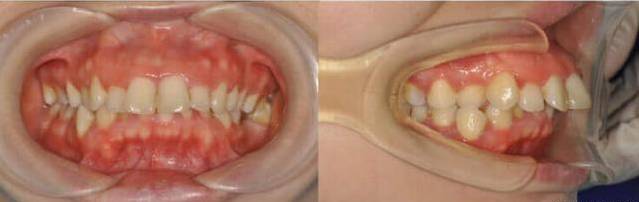

当人在微笑时,上颌前牙位置的牙龈暴露超过2毫米,我们称之为露龈笑。可能很多小伙伴笑起来从来没有在意过,但它确确实实很影响一个人的气质。它不仅会破坏面部的和谐美观,也会为当事人带来一定的心理负担。露龈笑的原因主要有两个:一个是唇的问题,另一个就是牙槽骨的问题。临床上解决露龈笑之前,先要检查分析患者为什么会有露龈笑的问题。如果是因为牙槽骨垂直向生长过度,这个就可以通过牙齿矫正来解决,通过种植钉把前牙压低来矫正。就是深受露龈笑的困扰,从正面来看牙龈暴露过多,笑起来很不好看,从侧面来看嘴凸明显,很影响人整体的气质。

同时牙齿有一定的拥挤,覆合很深。

通过拔牙矫正和种植钉,把前牙压低,改善露龈笑,内收门牙,排齐牙齿调整咬合。